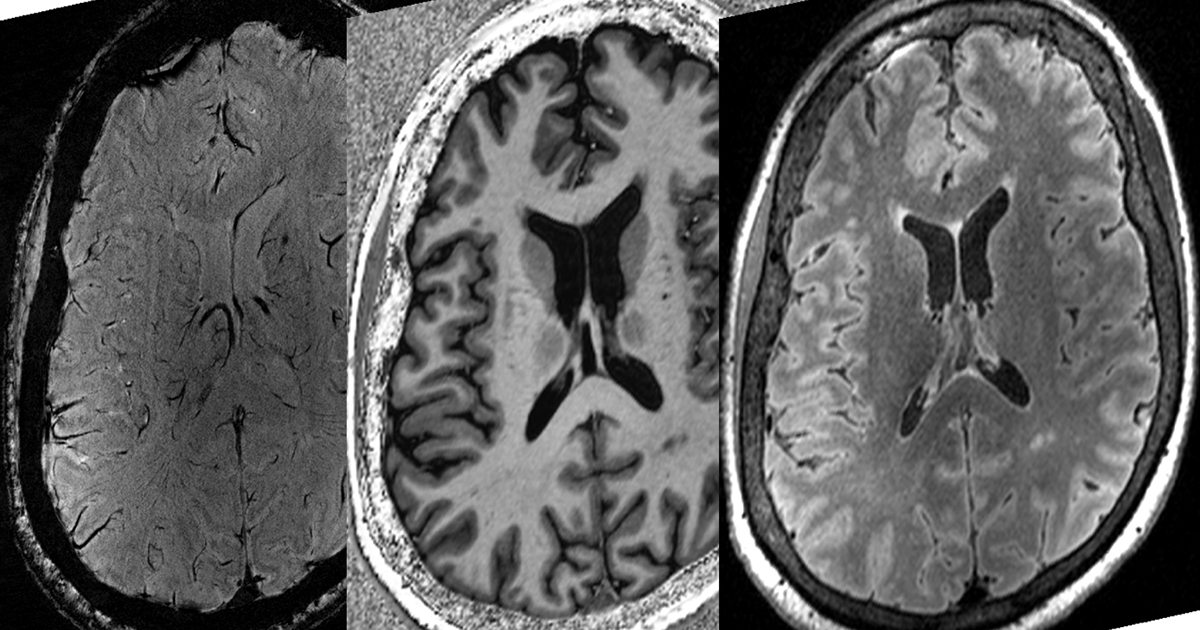

AI creates highresolution brain images from lowfield strength MR When Was Brain Imaging Invented The first step in the path towards obtaining a complete image of the human brain began on november 8, 1895, with a. Berger decided to measure the brain’s electrical activity in. The inspiration for modern mri brain scanners was built before world war i began, the titanic sank, and humans took flight. The eeg was invented by berger in 1924. When Was Brain Imaging Invented.

Exploring the Brain How Are Brain Images Made with MRI? UCSF Radiology When Was Brain Imaging Invented The eeg was invented by berger in 1924 and is a neuroimaging test that is used to detect electrical activity in the brain. Berger decided to measure the brain’s electrical activity in. Now neuroscientists are trying to give its inventor. Hounsfield never made it to egypt, but his invention did. Human functional brain mapping as we presently know it began. When Was Brain Imaging Invented.